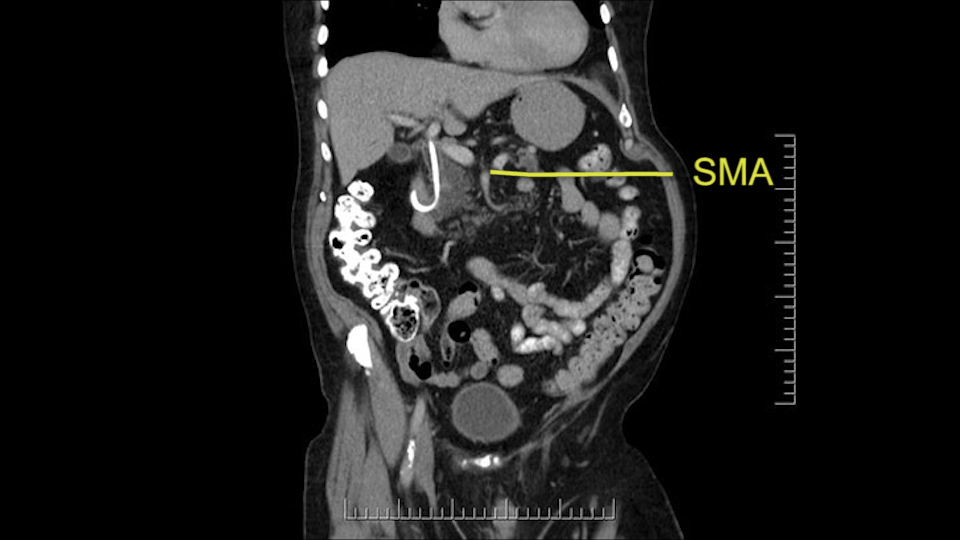

Then either through the coronal or the axial, I’ll do both. Look at the SMA -which is here- I had already looked at it and I don’t see any involvement. There’s the SMA with a nice fat plane between the SMA and the tumor. Over here you can see on the axial, there’s the SMA. Everything on the right side of the SMA has got some nice black around it, which is fat, which means probably no tumor [no tumor, no tumor]. Follow it up to the origin, coming off the aorta. So those are the two technical things that I worry about: the SMA and the SMV.

To plan a pancreatoduodenectomy, we start by reviewing the vascular anatomy, especially the origin of the celiac trunk, here, in front of the aorta, looking for any evidence of stenosis. In addition, we look at the origin of the superior mesenteric artery, to look for any branches, and any replaced right hepatic arteries coming from the superior mesenteric artery; which does occur in about 12% of the population.

The next thing we always evaluate, although we do not expect invasion to the portal veins in this case, we must always trace the path of the portal vein, in both directions, from top to bottom. The splenoportal confluence and the superior mesenteric vein, which in this case does not appear to be compromised.